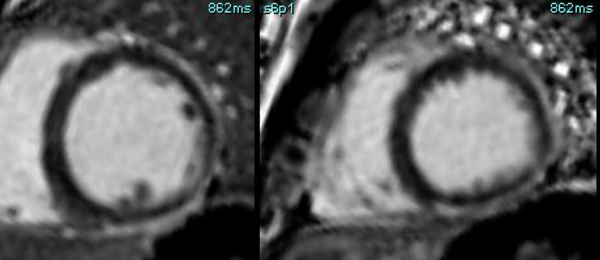

Non-Ischemic Cardiomyopathy

A lecture describing the role of CMR in the various non-ischemic cardiomyopathies